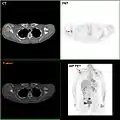

F-18 FDG PET/CT: A breast cancer metastasis to the right scapula

- Where available, imaging studies may be employed as part of the staging process in select cases to look for signs of metastatic cancer. However, in cases of breast cancer with low risk for metastasis, the risks associated with PET scans, CT scans, or bone scans outweigh the possible benefits, as these procedures expose the person to a substantial amount of potentially dangerous ionizing radiation.[96][97]